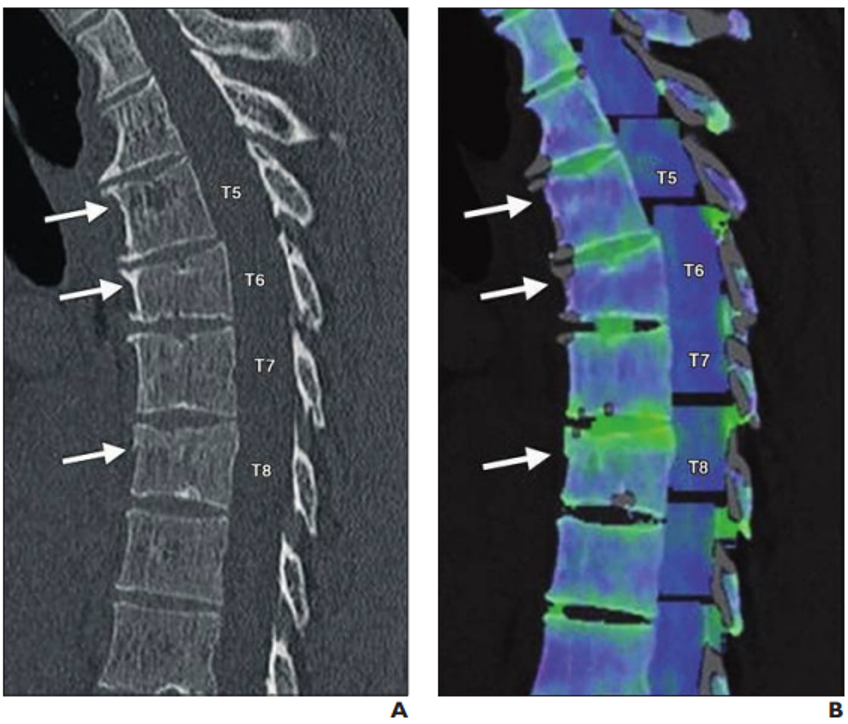

A, Sagittal reformatted bone window CT image of thoracic spine shows wedge-shaped deformity at T6 and subtle superior endplate deformities at T5 and T8. Arrows denote deformities. B, Color-coded dual-energy CT shows only T8 deformity is associated with bone marrow edema; T5 and T6 deformities likely represent chronic fractures. Arrows denote deformities.